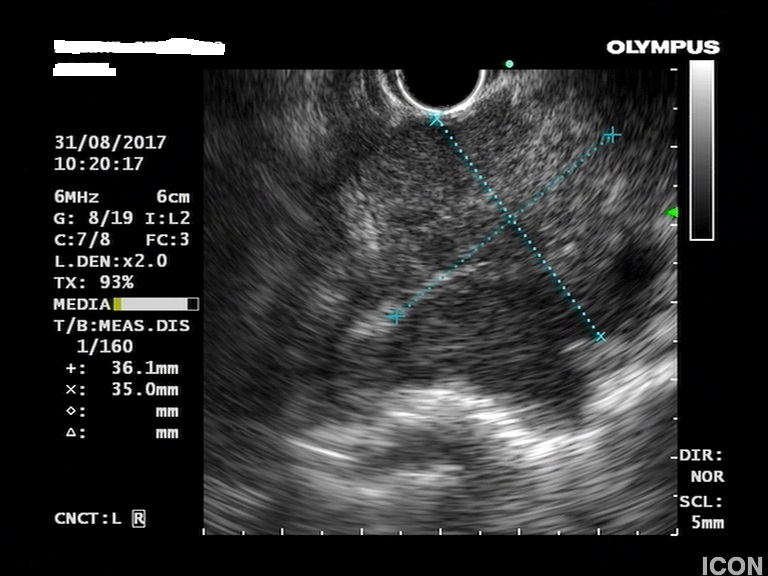

Γυναίκα 58 ετών, υποβλήθηκε προληπτικά σε υπέρηχο άνω κοιλίας όπου διαπιστώθηκε μια κύστη στην κεφαλή του παγκρέατος. Το εύρημα επιβεβαιώθηκε σε μαγνητική τομογραφία (MRI/MRCP) που δεν έδειξε άλλα παθολογικά ευρήματα στο πάγκρεας. Ο ενδοσκοπικός υπέρηχος έδειξε μια δίχωρη κύστη, διαστάσεων 6,5Χ12,5 χιλ, στην παγκρεατική κεφαλή.

Η κύστη είχε επικοινωνία με κλάδο του παγκρεατικού πόρου, ενώ ο μείζων παγκρεατικός πόρος ήταν φυσιολογικής διαμέτρου σε όλη την πορεία του. Επίσης, διαπιστώθηκε δεύτερη κύστη διαμέτρου 2,5χιλ στο σώμα του παγκρέατος που δεν είχε απεικονιστεί στην MRI.

Κύστη κεφαλής παγκρέατος